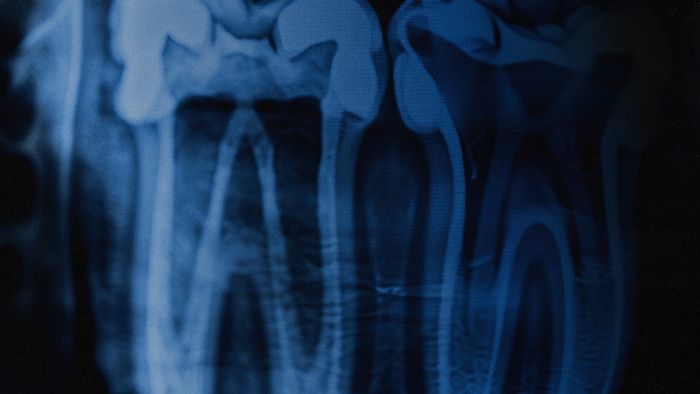

У полоні ворог намагається зламати людину не лише психологічно, а й фізично. Обличчя та зуби часто стають ціллю для катувань — за статистикою, кожен третій, хто пройшов через тортури, має важкі травми щелепи.

● Повну діагностику та складання плану реконструкції щелепи;